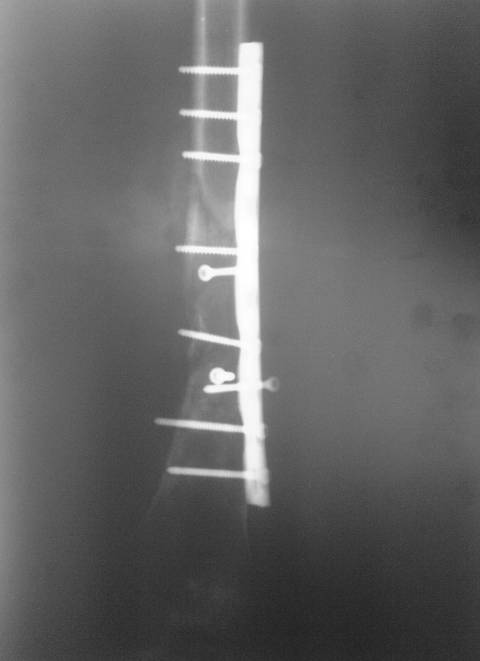

Оперирована в январе 2007 года по выходе из комы и восстановления витальных функций. Накостный остеосинтез DCP-LC. Снимки прилагаются.

Через 4 месяца стали беспокоить боли и деформациябедра. На снимке угловая деформация AP - варус 11 град.; lateral - 29 град. Объем движений в коленном суставе: ограничение сгибания до 90 град. Локально - патологическая подвижность в нижней трети бедра. Локальная гипертермия, отек мягких тканей. Гиперемии нет. Передвигалась на костылях.